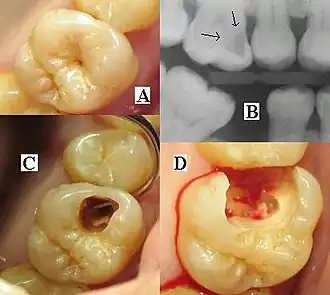

| Destruction of a tooth by dental caries and disease | |

The presentation of caries is highly variable. However, the risk factors and stages of development are similar. Initially, it may appear as a small chalky area (smooth surface caries), which may eventually develop into a large cavitation. Sometimes caries may be directly visible. However, other methods of detection, such as X-rays, are used for less visible areas of teeth and to judge the extent of destruction. Lasers for detecting caries allow detection without ionizing radiation and are now used for the detection of interproximal decay (between the teeth).

Primary diagnosis involves inspection of all visible tooth surfaces using a good light source, dental mirror, and explorer. Dental radiographs (X-rays) may show dental caries before it is otherwise visible, in particular caries between the teeth. Large areas of dental caries are often apparent to the naked eye, but smaller lesions can be difficult to identify. Visual and tactile inspection, along with radiographs, are employed frequently among dentists, in particular to diagnose pit and fissure caries.[89] Early, uncavitated caries is often diagnosed by blowing air across the suspect surface, which removes moisture and changes the optical properties of the unmineralized enamel.

At times, pit and fissure caries may be difficult to detect. Bacteria can penetrate the enamel to reach dentin, but then the outer surface may remineralize, especially if fluoride is present.[91] These caries, sometimes referred to as "hidden caries", will still be visible on X-ray radiographs, but visual examination of the tooth would show the enamel intact or minimally perforated.